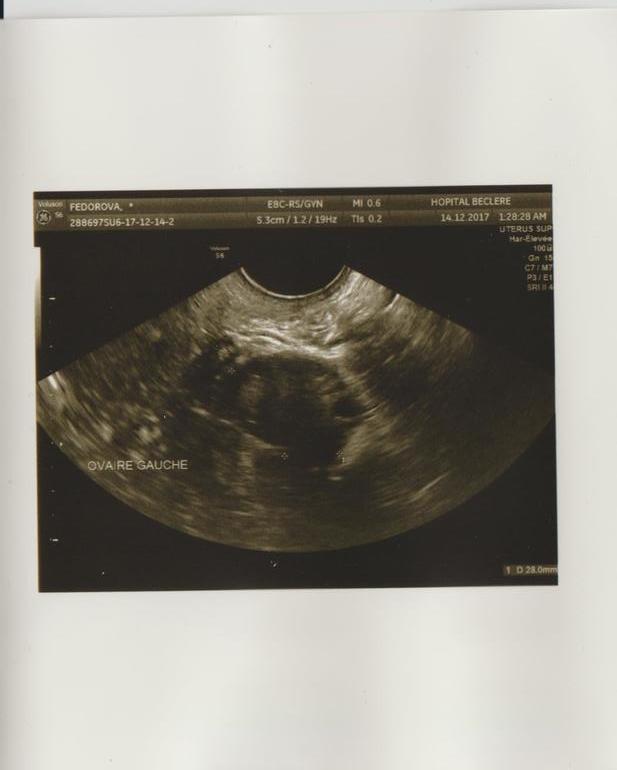

Правый, левый. И в углу видимо размеры, диаметр чего-то..н5онятно чего, наверное фолликула? На какой дц делалаи? Вижу вооде эндометри на втором фото... очень интересное конечно дело...у себя записи делают они?

никаких записей. по мнению глав врача- первый день цикла. у меня кровит, но очень скудно и светло-розовый цвет. я обратилась к врачу, так как это не типично для меня и в прошлом цикле приходилось останавливать кровотечение.

в общем мне вручили УЗИ и послали домой с выводами, что это начало месячных.

Нет расшифровки . На словах врач сказала начало цикла.

Но у меня есть основани не доверять ее выводам и спросить тут на форуме если кто нибудь что то в этом понимает